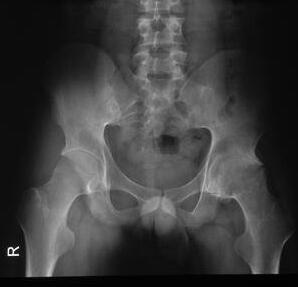

临床检查:背部弯曲严重,左眼视力4.0、患有虹膜炎;X片检查显示骶髋关节和脊柱融合,关节遭到严重破坏、增生硬化、骨质明显疏松、关节完全强直;实验室检查:红细胞沉降率达50mm/h, C反应蛋白(CRP) 高达50mg/l。

(图:X线片显示骶髋关节融合,完全强直)